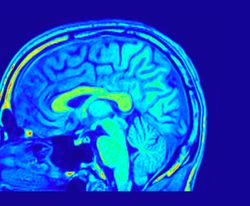

neuroscience